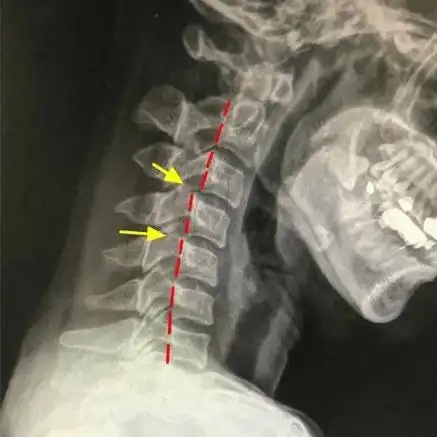

生理曲度变直 学习,补课,网课,同时户外运动减少,孩子脖子经常向前倾

严重的异状颈椎 手法小心

颈椎就是脖子里的骨头,在身体的最上面,它是身体最灵活的关节,也因为